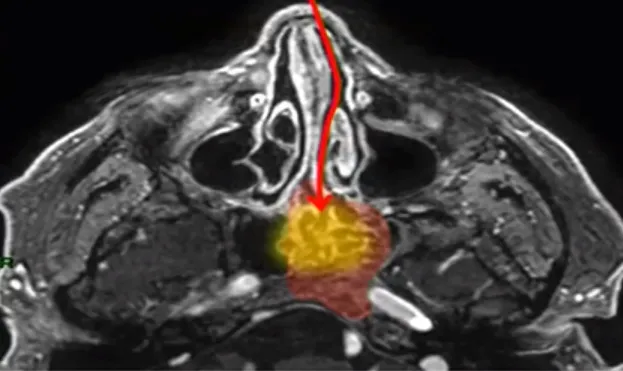

那么,在经鼻内镜手术的时候,就需要尽可能采取更温和、更精准的方式。借助人体自然的鼻腔通道,在不破坏周围重要结构的前提下切除肿瘤。INC福教授在技术实践的初期,就是这样做的——通过创造一个狭窄但足够操作的手术通道,精准抵达病灶。

上面那个动图是不是不够直观,那看福教授列出的两幅图对比:

微侵袭经鼻神经内镜入路,对鼻腔结构破坏更少,术后并发症更少。

而开放情况下,很明显出现了和李类似的情况,鼻腔结构没了。

福教授:“鼻腔的结构,内镜手术前是什么样子,手术后也应该维持原样!”

如果不这样做,就意味着要采用更开放、更侵入的方式,那样会对鼻腔的正常结构和功能造成不可逆的损伤。福教授想做的,正是在“切除”与“保护”之间,找到那个至关重要的平衡。